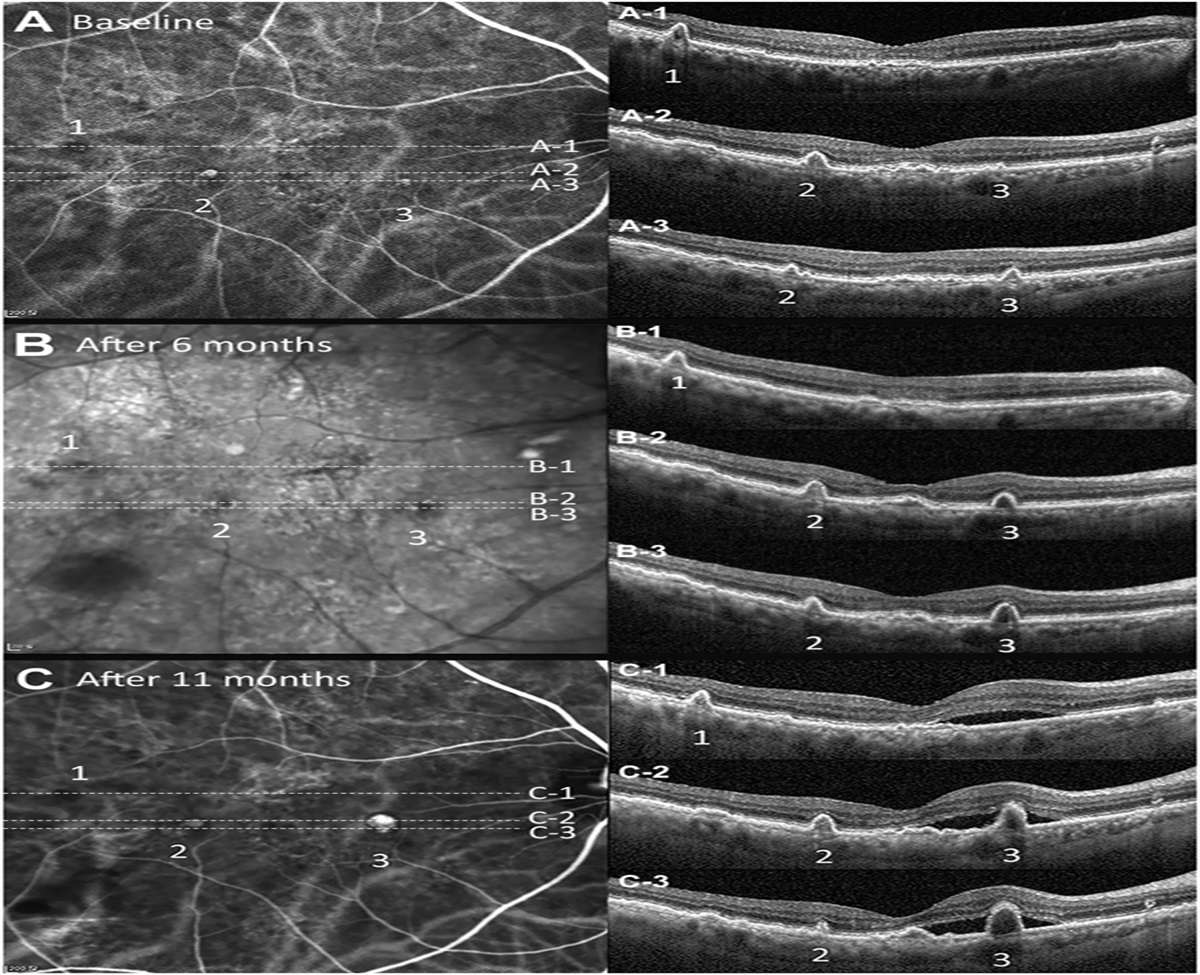

Cloudy Vitelliform Submaculopathy as an Early Sign of Primary Vitreoretinal Lymphoma

Department of Ophthalmology, Shanghai General Hospital, School of Medicine, Shanghai Jiao Tong University, National...